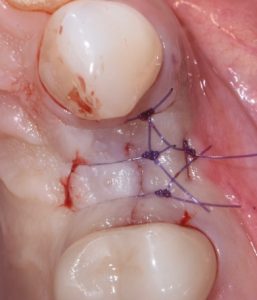

This video demonstrates alveolar ridge preservation following atraumatic surgical extraction of an endodontically treated tooth. Emphasis is placed on minimizing surgical trauma to preserve existing hard and soft tissues.

The case features flap management in the presence of a buccal dehiscence, followed by bone graft placement and stabilization using a dense polytetrafluoroethylene (d-PTFE) membrane. Surgical principles, membrane selection, and handling techniques are discussed to optimize ridge dimensions and facilitate future implant placement.